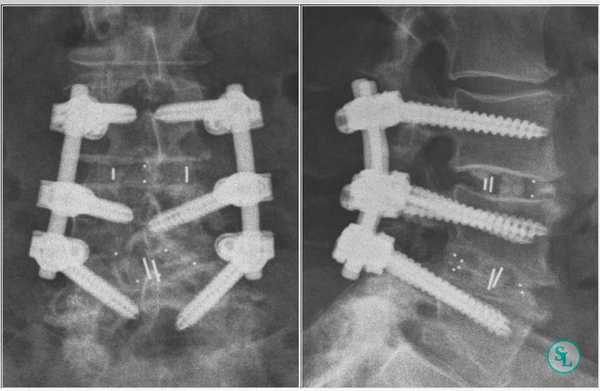

В 1-й группе пациентов выполняли вентральный внебрюшинный доступ к уровню LV—SI, тотальную дискэктомию с передней декомпрессией дурального мешка, во 2-й группе — декомпрессию дурального мешка и корешков дорзальным срединным доступом с установкой межтелового кейджа и транспедикулярной винтовой фиксацией для формирования спондилодеза.

Во 2-й группе пациентов показатели угла операционного действия колебались от 79 до 95°, в среднем 87,1±8°. Угол оси операционного действия колебался от 75 до 89° и составил в среднем 82,1±4,1°. Длительность операции колебалось от 140 до 242 мин, в среднем 210±23 мин. Длина операционной раны колебалась от 80 до 140 мм, в среднем 108±14 мм. Глубина операционной раны колебалась от 70 до 130 мм и составила в среднем 103±21 мм. Кровопотеря колебалась от 80 до 760 мл, в среднем 440±23,5 мл. Такая большая кровопотеря обусловлена работой в эпидуральном пространстве с наличием большого количества расширенных эпидуральных вен на фоне рубцово-спаечного процесса.

Клинический пример. Пациентка Т., 42 года, обратилась с признаками рецидива грыжи диска LV—SI, подтвержденной данными магнитно-резонансной томографий. В анамнезе перенесенный перитонит, и как следствие — спаечный процесс в брюшной полости и по левому флангу забрюшинно в местах, в которых стояли дренажи. В связи с этим пациентке выполнена операция из дорзального доступа: декомпрессия дурального мешка, корешков LV, SI справа, удаление рецидивной грыжи с межтеловым корпородезом кейджем и транспедикулярной фиксацией LV—SI. Угол операционного действия составил 84°, длина раны — 98 мм, глубина раны — 74 мм, угол наклона оси операционного действия составил 82°. При этом, несмотря на удовлетворительный обзор и комфортные условия для выполнения операции, доступ осуществлялся с техническими трудностями через рубцово-измененные ткани, что потребовало длительного и деликатного выделения нервных корешков на фоне кровотечения из эпидуральных вен, в связи с чем время операции составило 167 мин, кровопотеря — 430 мл.